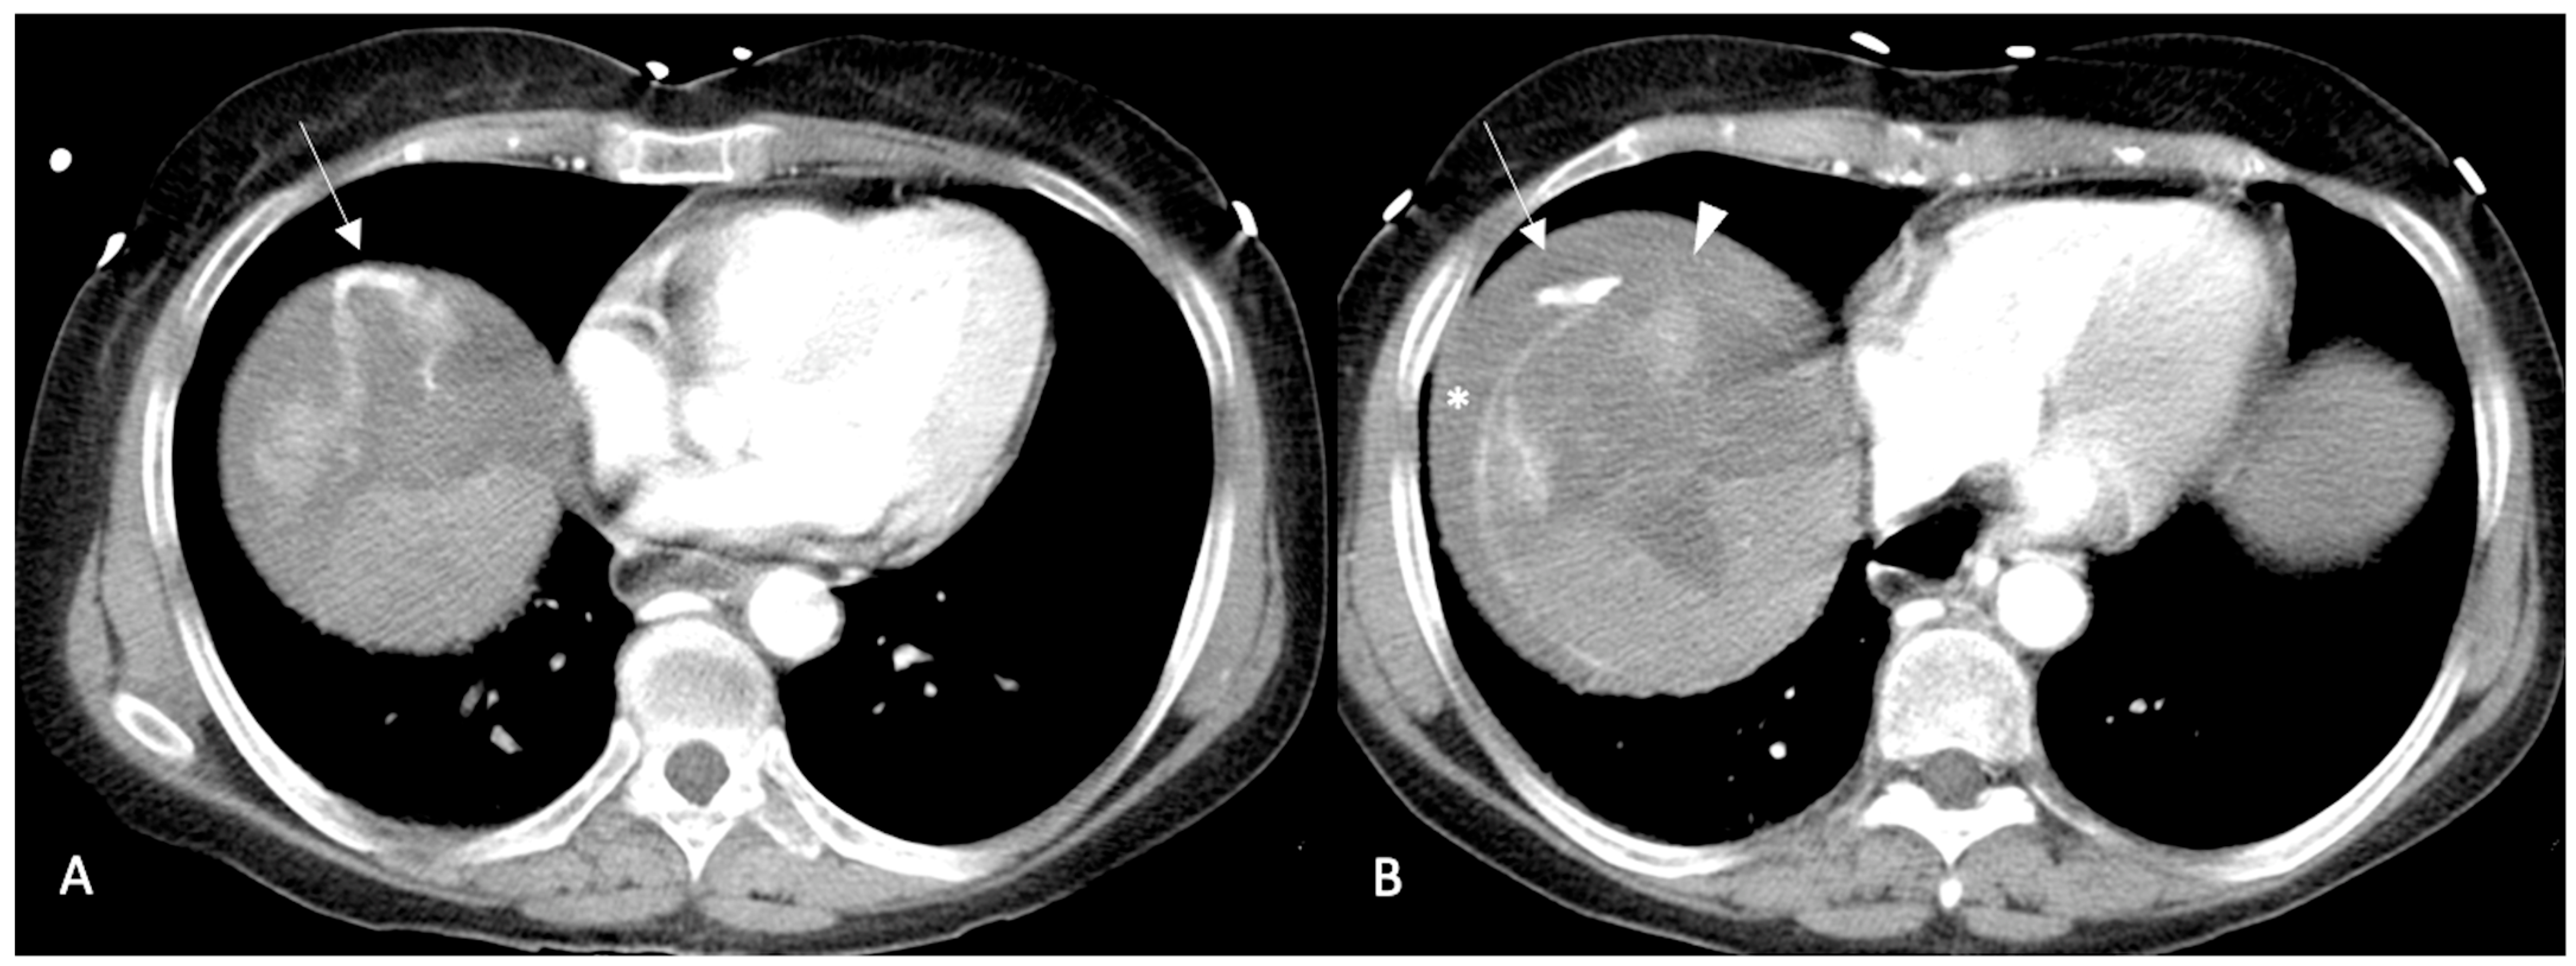

- Kim, H.C.; Yang, D.M.; Jin, W.; Park, S.J. The Various Manifestations of Ruptured Hepatocellular Carcinoma: CT Imaging Findings. Abdom. Imaging 2008, 33, 633–642. [Google Scholar] [CrossRef]

- Ilyas, M.; Bashir, M.; Robbani, I.; Rasool, S.R.; Shera, F.A.; Hamid, I. Sentinel Clot Sign in Hemoperitoneum. Abdom. Radiol. 2019, 44, 1955–1956. [Google Scholar] [CrossRef]

- Orwig, D.; Federle, M.P. Localized Clotted Blood as Evidence of Visceral Trauma on CT: The Sentinel Clot Sign. AJR Am. J. Roentgenol. 1989, 153, 747–749. [Google Scholar] [CrossRef]